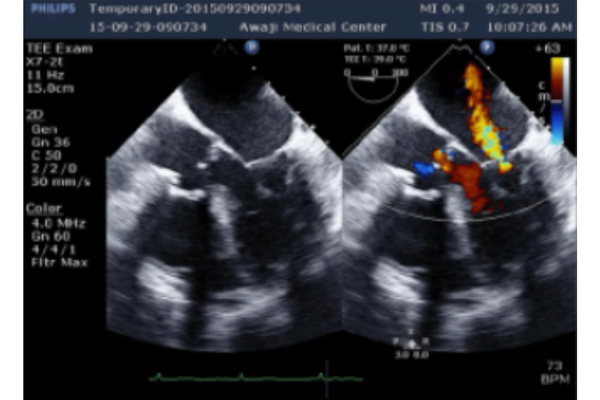

Hở van hai lá trong siêu âm tim qua thực quản

Hở van hai lá cấp luôn có những triệu chứng cơ năng nặng nề. Khám lâm sàng ở mỏm tim thường dễ bỏ sót, do thất trái với kích thước bình thường không hề gây mỏm tim đập tăng động. Tiếng thổi tâm thu do hở van hai lá cấp tính nhiều khi không kéo dài hết thì tâm thu thậm chí có lúc không nghe thấy. Siêu âm tim qua thành ngực giúp chẩn đoán mức độ hở van hai lá, cơ chế hở van, đánh giá chức năng thất trái, chức năng thất phải và áp lực động mạch phổi….

1.2 Cách đánh giá mức độ nặng của HoHL bằng siêu âm qua thực quản

- Hướng dòng phụt ngược: Trung tâm hay lệch tâm về phía thành nhĩ trái.

- Độ rộng của dòng phụt ngược tại gốc, ≥ 0,5 cm ở góc 120°, được gọi là “ vena contracta ”

Sa van hai lá gây ra hở hai lá lệch tâm, do đó sa lá sau sẽ tạo ra dòng phụt hướng về phía trước và ngược lại. Lưu ý: Khi dòng phụt của hở hai lá lan tới thành nhĩ trái thì cần đánh giá mức độ nặng của hở hai lá tăng lên. Đối với các tĩnh mạch phổi trái và phải cần dùng Doppler xung để kiểm tra xem có đảo ngược phổ tâm thu hay không.